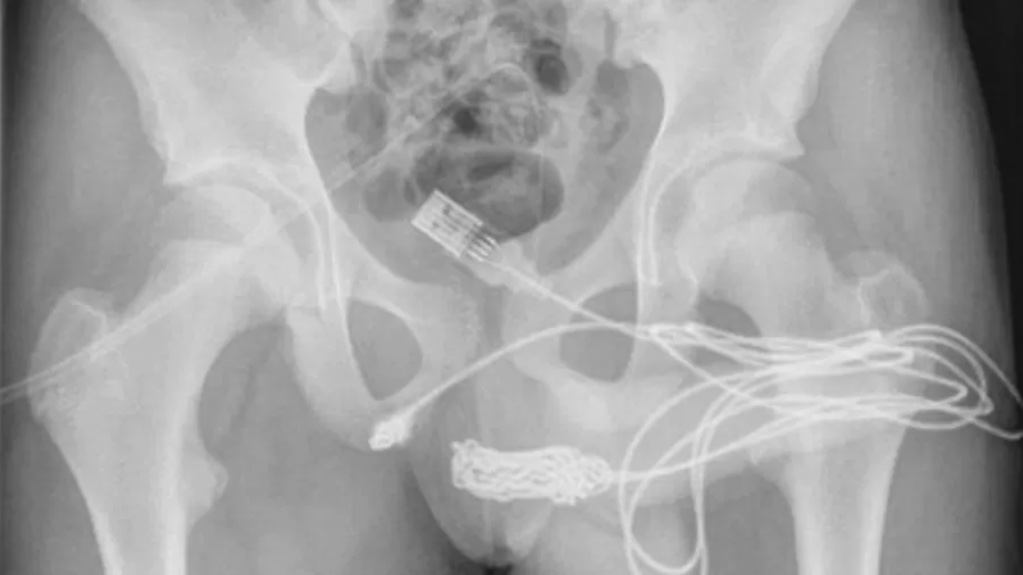

Na radiografia feita no hospital, era possível ver que o cabo ficou com alguns nós e ficou emaranhado na uretra.

Para tirar o objeto, os médicos tentar puxar o cabo com uma haste de metal, mas o nó impedia a saída, então foi necessário fazer um corte entre a genitália e o ânus para que pudessem chegar ao cabo por baixo.